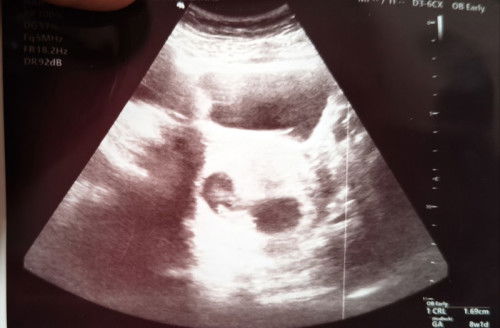

ADE BAYANG DI BELAKANG JANIN

Hi mommies saya nak tnya smlm saya pergi scan 8 weeks, time scan tu Dr pun mcm pelik ad bayang blkg janin tu.. sbb saiz bayang tu sama dgn saiz janin yg warna putih terang tu.. bayang tu mcm malap sikit ...Ade yg pernh alami mcm ni tak sbb saya first mom.. adakah possibility utk kembar atau apa dia sebenarnya tu..